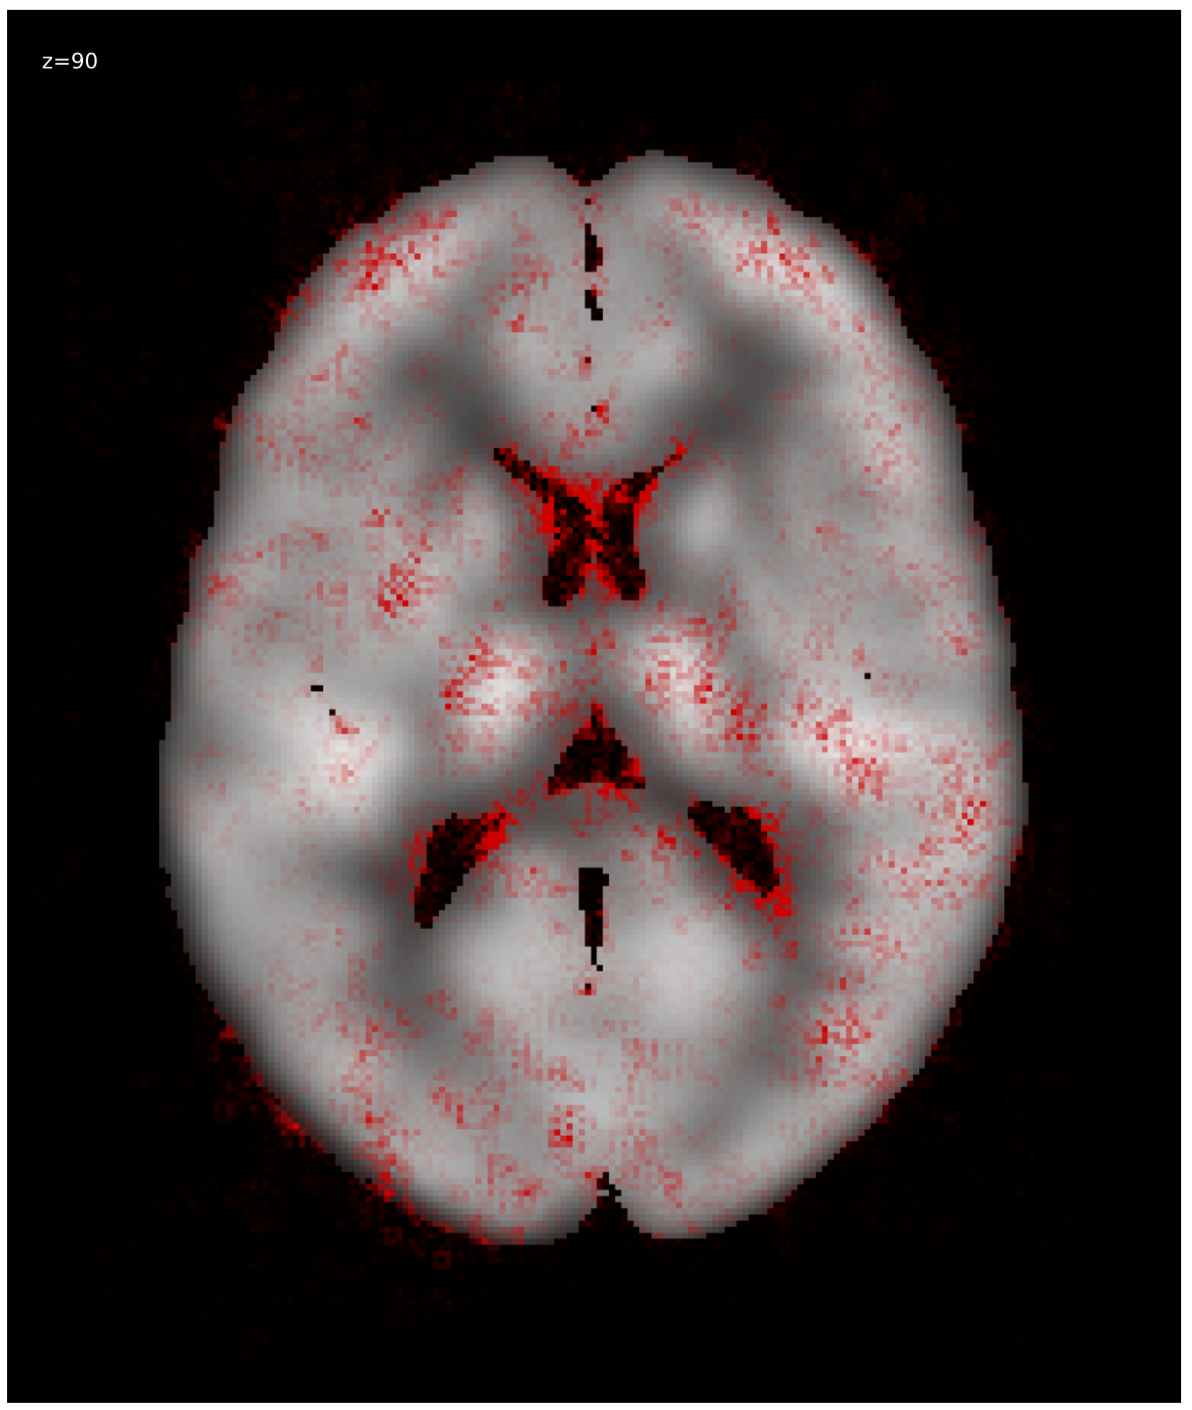

We generated relevance heatmaps for all visualizations methods, averaged over AD PET images in the test dataset. Figure 2 presents the visual comparison of these five methods. The red areas/dots indicate that regions were important for the decision making of the 3D-CNN model. From the result, we can see that all the visualization focuses mostly on similar brain regions. There are some differences, such as the heatmaps generated for the gradient-based methods are distributed. The heatmaps highlight the areas that the CNN network is most susceptible. For the LRP method, the heatmap shows the average relevance of each voxel for contributing to the AD diagnosis score. The heatmaps generated by the occlusion based methods are more focused on the specific regions and cannot administer with large areas of distributed relevance. The reason behind the issue is the occlusion path was not able to cover those areas (for example, the cortex) completely. Brain area occlusion presents very high relevance for the temporal lobe. Since in this method, only one area is covered at a time, that can cause such high importance for one region and minimal relevance for other regions.